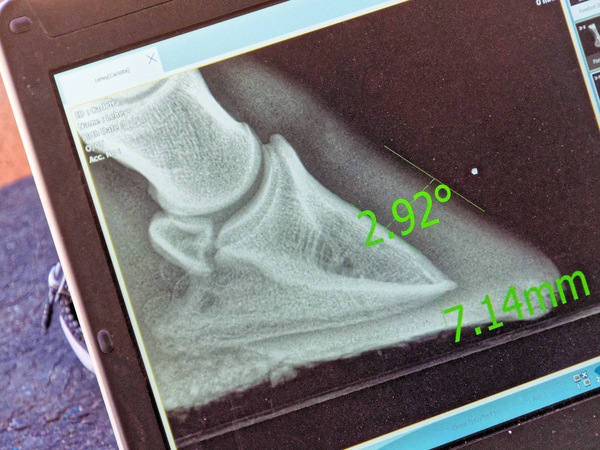

Examining Carlotta's hooves, analemma

https://lemis.nyc3.digitaloceanspaces.com/grog/Photos/20211231/small/Carlotta-vet-check-2.jpeg

Image title: Carlotta vet check 2

Dimensions: 602 x 449, 160 kB

Dimensions of original: 4633 x 3456, 5349 kB